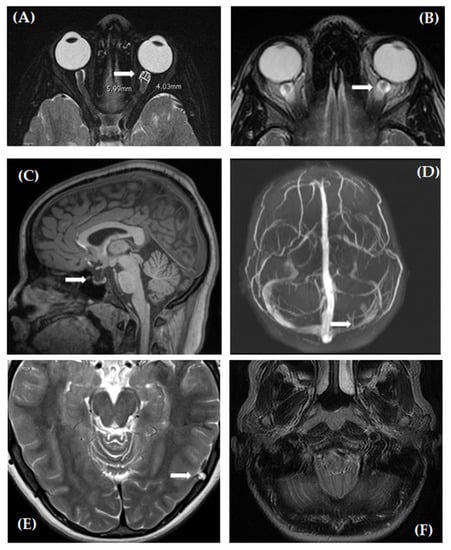

| Perioptic subarachnoid space diameter, mm | 5.7 ± 0.7 | 5.0 ± 0.6 | <0.001 |

| Posterior globe flattening (%) | 28 (74) | 0 (0) | <0.001 |

| Optic nerve protrusion (%) | 17 (45) | 0 (0) | <0.001 |

| Empty sella (%) | 20 (53) | 2 (8) | <0.001 |

| Dural Venus Sinus Abnormalities (%) | 20/29 (69) | 9 (38) | 0.029 |